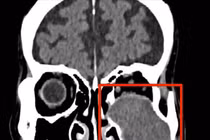

Bệnh viện Đa khoa tỉnh Quảng Trị cho biết vừa phẫu thuật thành công cho một bệnh nhân bị u nhầy xoang hàm biến chứng nặng, gây tiêu xương thành xoang hàm và ăn mòn xương sàn ổ mắt.

Hình ảnh chụp phim cho thấy khối u ăn mòn tiêu xương sàn ổ mắt. Ảnh nguồn tienphong.vn